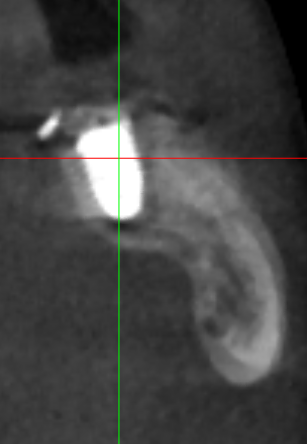

Irouil Опубликовано 15 июля, 2023 Поделиться Опубликовано 15 июля, 2023 Интересно, одномоментно в лунку дистального корня не зашло бы? Предположу, что либо ангуляция вышла бы экстремальной, либо слишком близко к вестибулярной стенке пришлось бы ставить Вообще, эти случаи с выраженным поднутрением в боковых отделах нижней челюсти достаточно коварные, на мой взгляд, с точки зрения позиционирования 1 Ссылка на комментарий

Doc Опубликовано 15 июля, 2023 Поделиться Опубликовано 15 июля, 2023 Раньше мы очень берегли каждую семерку, если она даже под приличным углом стояли, но с опытом поняли, что из-за поднутрений прогноз и у имплантатов сильно ухудшается и у самих семерок. Теперь предлагаем пациенту альтернативу: либо идет к ортодонтам, ставит минивинты и тащит семерку на место, либо удаляем и ставим в идеальную позицию два имплантата с хорошим прогнозом. В данном случае угол есть, но не смертельный. Жить будет. 3 Ссылка на комментарий

Irouil Опубликовано 15 июля, 2023 Поделиться Опубликовано 15 июля, 2023 Я, честно говоря, о другом поднутрении говорил) о поднижнечелюстном, куда заплывает одноименная слюнная железа. Некоторые авторы рекомендуют и даже показывают успешные кейсы аугментации этой области, ибо в экстремальных случаях аугментировать крестально просто некуда - но две попытки отслойки до сих пор у меня заканчивались разрывом надкостницы и выходом в подмышечную область, что чревато. Интересно, пробует ли кто-то из форумчан смещать железу и использовать это пространство для твердотканных аугментаций Ссылка на комментарий

TIGER Опубликовано 15 июля, 2023 Автор Поделиться Опубликовано 15 июля, 2023 @Irouil было бы сложно стабилизировать в этих условиях,в случае неуда ситуация усугблялась,решил пойти по пути сохранения тканей,дал организму самому регенирировать,при имплантации добавил чуть тканей @Doc ещё Миш писал в книге о минусах имплантации семёрок кстати 1 Ссылка на комментарий